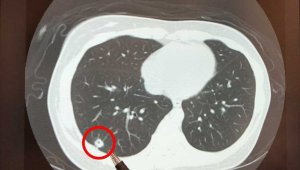

- 吓坏14亿人!打科兴疫苗后出现肺结节 中共紧急“辟谣”?(组图)